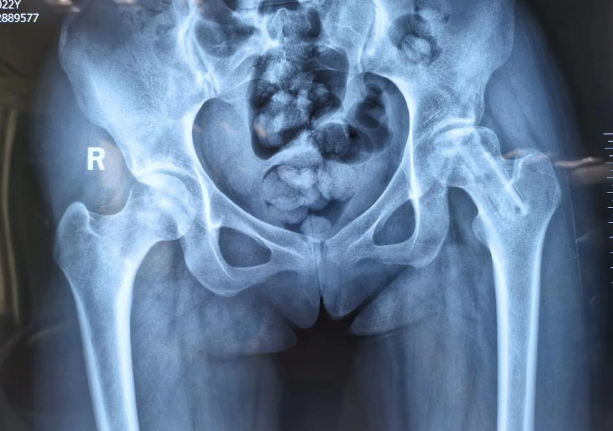

我接过那叠沉重的资料,一张张CT影像上,他左侧的股骨头已然有了塌陷的苗头,像一颗被虫蛀蚀的果实。我深知这个诊断意味着什么——那是日日夜夜、如影随形的髋部剧痛,是关节像生锈门轴般难以活动的僵硬,是行走能力可能逐渐丧失的恐惧。这些年,他求医的足迹遍布南北,中药的苦涩、理疗的炙热、各种名目繁多的“疗法”,都已尝遍。希望一次次燃起,又一次次在复查的影像和持续的疼痛中化为灰烬。

我给他倒了一杯水,沉吟片刻,决定坦诚相告。“老林,牛骨胶原蛋白肽,本质上是一种高级的营养补充剂。它就像给你这受损的骨骼,空投最精锐的‘建筑工兵’和‘优质建材’。”我指着片子上那个发暗的股骨头区域,“对于你这种情况,任何方法的效果都‘因人而异’。但我能肯定的是,它核心的作用是‘修复’——为你坏死区域周围那些濒临饿死、功能受损的骨细胞、软骨细胞,提供它们再生所必需的、最直接的材料。它不是手术刀,不能瞬间替换坏死的部分;它更像是‘春雨’和‘养分’,目的是滋养、唤醒那些还有活力的‘土壤’,让它们自己强大起来,去修复、去包裹、去支撑。”

我沉浸到文献与研究中,试图解开这个“修复之谜”。股骨头坏死,本质是骨细胞因缺血而“饿死”,导致骨质流失、承重结构坍塌。传统治疗旨在延缓塌陷或进行置换,而牛骨胶原蛋白肽,则开辟了一条“生物营养修复”的路径: